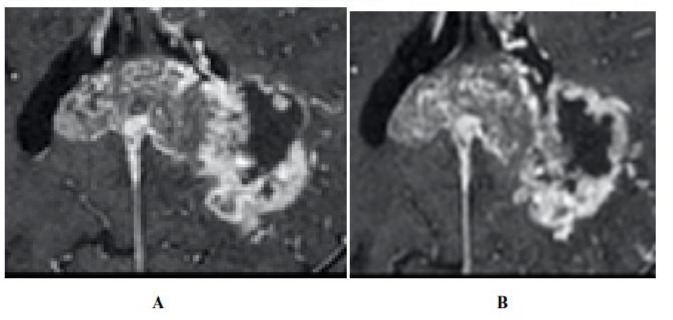

This classification scheme is also applied following radio/chemiotherapy to assess for changes in the volume of each compartment. A heterogeneous pattern colud be identified before treatment, with the majority of the tumour consisting of highly vascular regions. Following radio/chemiotherapy, the proportion of poorly vascularised tissue could increase indicating a disruption in the blood supply to the tumour (Figure1)[6]. Using the collective data archive, we can study the biological basis of these regions, and develop response/ prognostic models that combine imaging phenotypes with regional histopathology and molecular profiling of tissues [4].

Clinical utility of habitat imaging in glioblastoma: assessment of changes pre and post-radiotherapy. These figures demonstrate the clinical utility of habitat imaging in glioblastoma pre and post-radiotherapy

Figure 1:T1 with contrast demonstrates no significant changes in tumour anatomy pre treatment(A) and post treatment (B). [6]